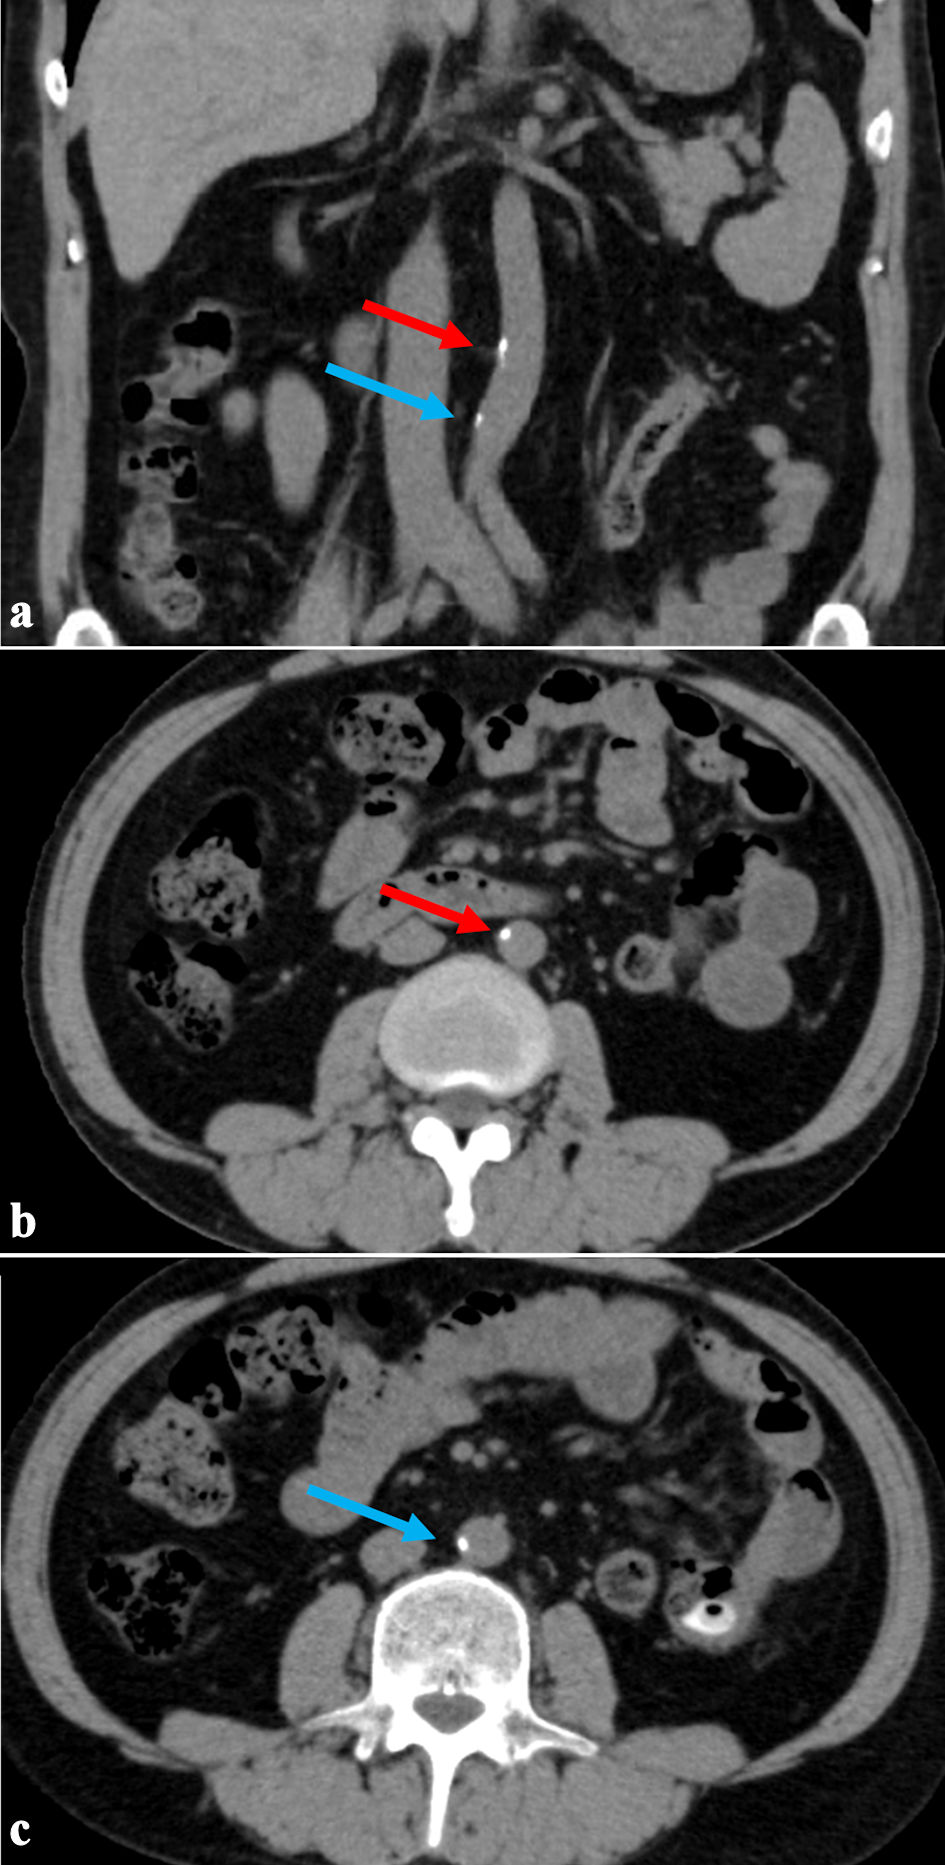

Click for large image

Figure 3. The second abdominal CT scan taken 34 years after initiating dialysis (5 years after the first CT scan). (a) Coronal section. (b, c) Axial sections showing abdominal aortic calcification area. The red arrow indicates the upper calcification area, and the blue arrow indicates the lower area. There has been little change in the calcified lesions after 5 years. CT: computed tomography.

A CT scan performed 29 years after initiating hemodialysis revealed vascular calcification in the abdominal aorta; however, the AACI was low at 5.8%. Five years later, the AACI increased slightly to 6.7%; however, no new vascular calcifications were observed in the thoracoabdominal aorta during these 5 years (Fig. 3b, c). However, calcification of the internal iliac artery was found, but there was no evidence of buttock claudication due to impaired blood flow in the internal iliac artery (Fig. 4).